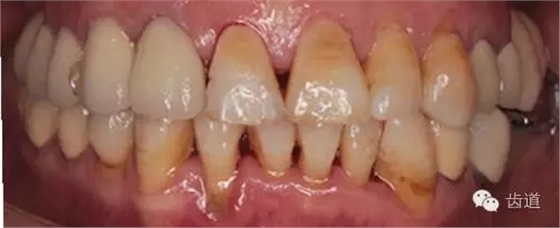

1、治療前

2、治療后

全口衛(wèi)生情況欠佳,可探及齦上及齦下牙結(jié)石,有牙齦探診出血,有牙齦退縮及牙周附著喪失。